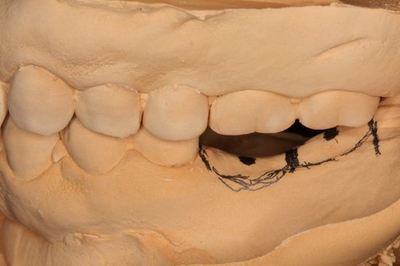

KaVoプロターevo7咬合器にマウントしました。

石膏はすべて超硬石膏(ニューフジロック)です。

このままでは第二大臼歯部分のクリアランスが足りません。

骨の修正を行い、クリアランス(顎間距離)を確保します。